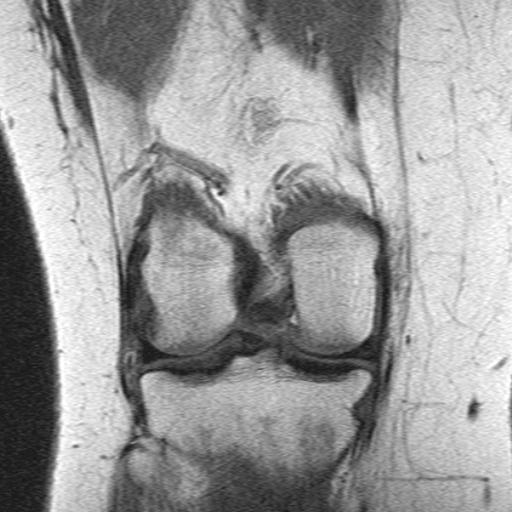

3.4. Результаты МРТ

Заживление связки было зафиксировано на МРТ через 6 месяцев (рис. 3). Мы оценили непрерывность и толщину передней крестообразной связки. В коленях, успешно пролеченных с помощью корсета ACL-Jack (), нормальный вид передней крестообразной связки был обнаружен в 36 (55%) коленях (рис. 4). Двадцать пять колен (38%) сохранили непрерывность передней крестообразной связки, но либо неправильную форму, либо более тонкий остаток, либо и то, и другое. Еще пять (7%) показали лишь минимальные остатки передней крестообразной связки. Ни у одного из неудачных пациентов в группе ACL-Jack не было нормального внешнего вида ACL. У двух пациентов (14%), успешно пролеченных в группе функционального лечения, передняя крестообразная связка выглядела нормально. Четыре (28%) сохранили непрерывность передней крестообразной связки, но либо неправильную форму, либо более тонкий остаток, либо и то, и другое.

Еще восемь (57%) показали лишь минимальные остатки передней крестообразной связки. Ни у одного из пациентов с неудачным исходом в группе функционального лечения не было нормального внешнего вида передней крестообразной связки.